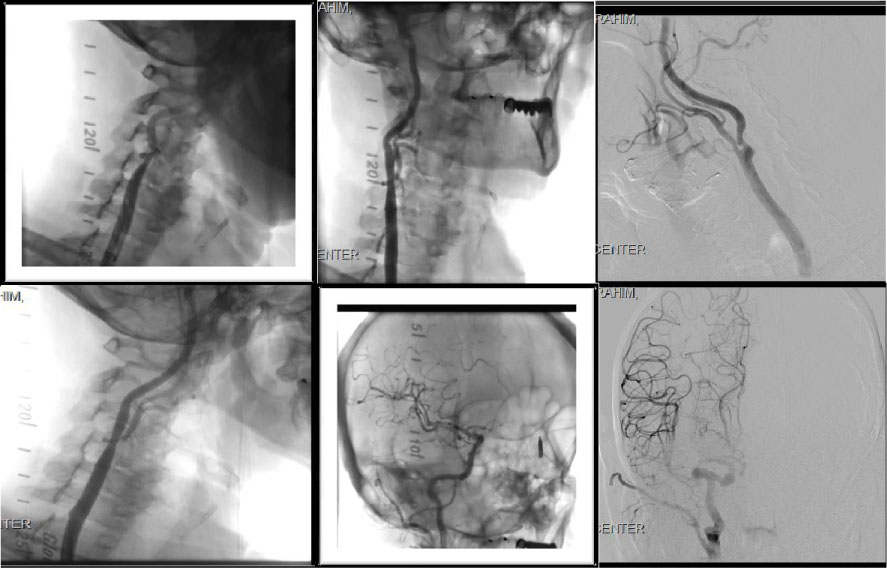

On the same setting Carotid Angiogram showed significant > 80% right ICA, with left carotid artery 60% stenosis. We proceeded with intervention also in the same setting, Successful right internal carotid artery angioplasty and stenting using 6 × 8 × 30 mm XACT self-expandable stent with Emboshield NAV 6 distal protection filter device, achieving excellent angiographic result with improved right cerebral perfusion on post stent angiogram (Figures 4).

Figure 4: Showing the R Carotid artery stenosis (pre-angioplasty) showing the R Carotid artery stenosis (Post-angioplasty) Cerebral Angiogram Post stenting of the R.T carotid artery showing improved right hemispheric circulation. View Figure 4